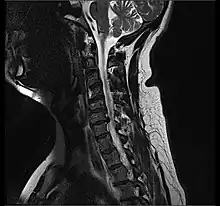

Cervical disc herniations occur in the neck, most often between the fifth and sixth (C5–6) and the sixth and seventh (C6–7) cervical vertebral bodies. There is an increased susceptibility amongst older (60+) patients to herniations higher in the neck, especially at C3–4.[23] Symptoms of cervical herniations may be felt in the back of the skull, the neck, shoulder girdle, scapula, arm, and hand.[24] The nerves of the cervical plexus and brachial plexus can be affected.[25]

- Magnetic resonance imaging is the gold standard study for confirming a suspected LDH. With a diagnostic accuracy of 97%, it is the most sensitive study to visualize a herniated disc due to its significant ability in soft tissue visualization. MRI also has higher inter-observer reliability than other imaging modalities. It suggests disc herniation when it shows an increased T2-weighted signal at the posterior 10% of the disc. Degenerative disc diseases have shown a correlation with Modic type 1 changes. When evaluating for postoperative lumbar radiculopathies, the recommendation is that the MRI is performed with contrast unless otherwise contraindicated. MRI is more effective than CT in distinguishing inflammatory, malignant, or inflammatory etiologies of LDH. It is indicated relatively early in the course of evaluation (<8 weeks) when the patient presents with relative indications like significant pain, neurological motor deficits, and cauda equina syndrome. Diffusion tensor imaging is a type of MRI sequence used for detecting microstructural changes in the nerve root. It may be beneficial in understanding the changes that occur after herniated lumbar disc compresses a nerve root, and might help in differentiating the patients that need surgical intervention. In patients with a high suspicion of radiculopathy due to lumbar disc herniation, yet the MRI is equivocal or negative, nerve conduction studies are indicated.[46] T2-weighted images allow for clear visualization of protruded disc material in the spinal canal.

MRI scan of cervical disc herniation between C5 and C6 vertebrae

MRI scan of cervical disc herniation between C6 and C7 vertebrae